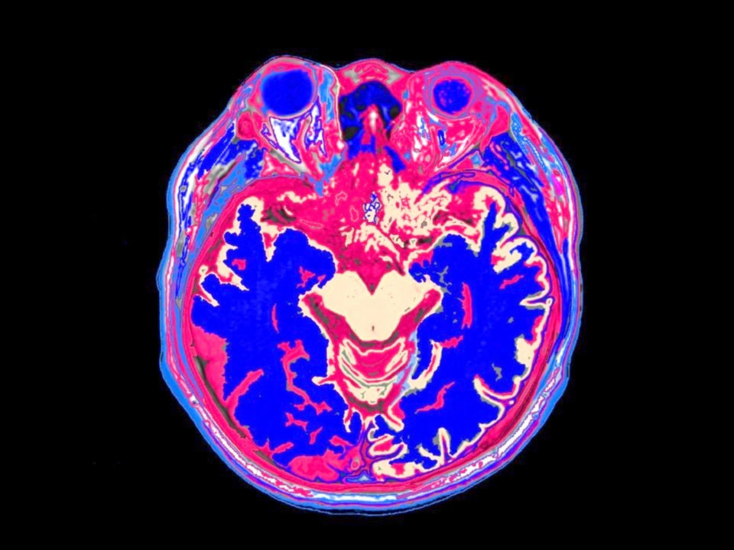

Ý thức đến từ đâu: Vỏ não, tiểu não hay một nơi sâu hơn chúng ta chưa biết?

Từ lâu, giới khoa học vẫn tin rằng vỏ não lớp ngoài cùng của bộ não là trung tâm tạo ra ý thức, nơi hình thành nhận thức, cảm xúc và suy nghĩ của con người. Nhưng nghiên cứu mới từ Đại học...